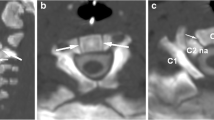

Osteopathia striata with cranial sclerosis (OSCS) is a rare but well-described pathology characterized by abnormalities in bone deposition in the axial and cranial skeleton as well as other abnormalities and associated deficits. These skeletal abnormalities can lead to significant intra-operative challenges for the surgeon and influence outcomes for the patient. In this report, we present a case of a patient with OSCS who was involved in a traumatic motor vehicle crash and underwent posterior cervico-thoracic fusion for a T4 chance fracture. Bony abnormalities in the cervico-thoracic spine presented a significant operative challenge due to alterations in bony anatomy and bone architecture. This case serves as an example of the challenges that the spine surgeon faces when dealing with OSCS, and highlights the differences between OSCS and commoner skeletal hyperplasias such as osteopetrosis.